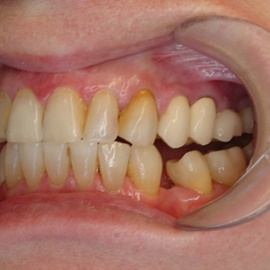

Pacjent z długą historią leczenia implantologicznego. Pierwsze implanty w pozycjach 23, 24 miał wkręcane w Warszawie przed 25 laty. Implant w pozycji górnego prawego kła ma agresywny gwint, ponieważ bezpośrednio po implantacji był obciążony (immediate loading) tymczasowym atachmentem ball abutmentv do stabilizacji tymczasowej protezy ruchomej. Kość szczęki regenerowana i odbudowywana etapami w całym górnym prawym kwadrancie. Pacjent planuje uzupełnić brakujące zęby 25, 26.